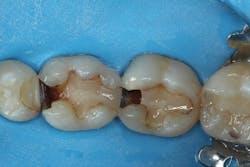

After removing the previous restorations, the distal axial wall of tooth No. 30 and the mesial axial wall of No. 31 had deep caries (figure 2). TheraCal LC (Bisco Dental)—a light-cured, resin-based liner containing calcium silicate (the active ingredient of MTA)—was placed over these areas of deep caries. A thin layer of the material was placed just at the areas of deep caries (figure 3) and light cured. Layers should be kept thin to ensure that the entire bulk of this opaque material cures, and placement should be limited to areas where needed in order to use the surrounding dentin for adhesive bonding. The dentin should be moist but not overly wet when TheraCal LC is applied to ensure that the material “sticks” to the tooth. Because this material is resin based, it is not necessary to cover this material with a separate resin-modified glass ionomer (RMGI) liner.

Figure 2: Deep caries remains on the distal axial wall of tooth No. 30 and the mesial axial wall of No. 31